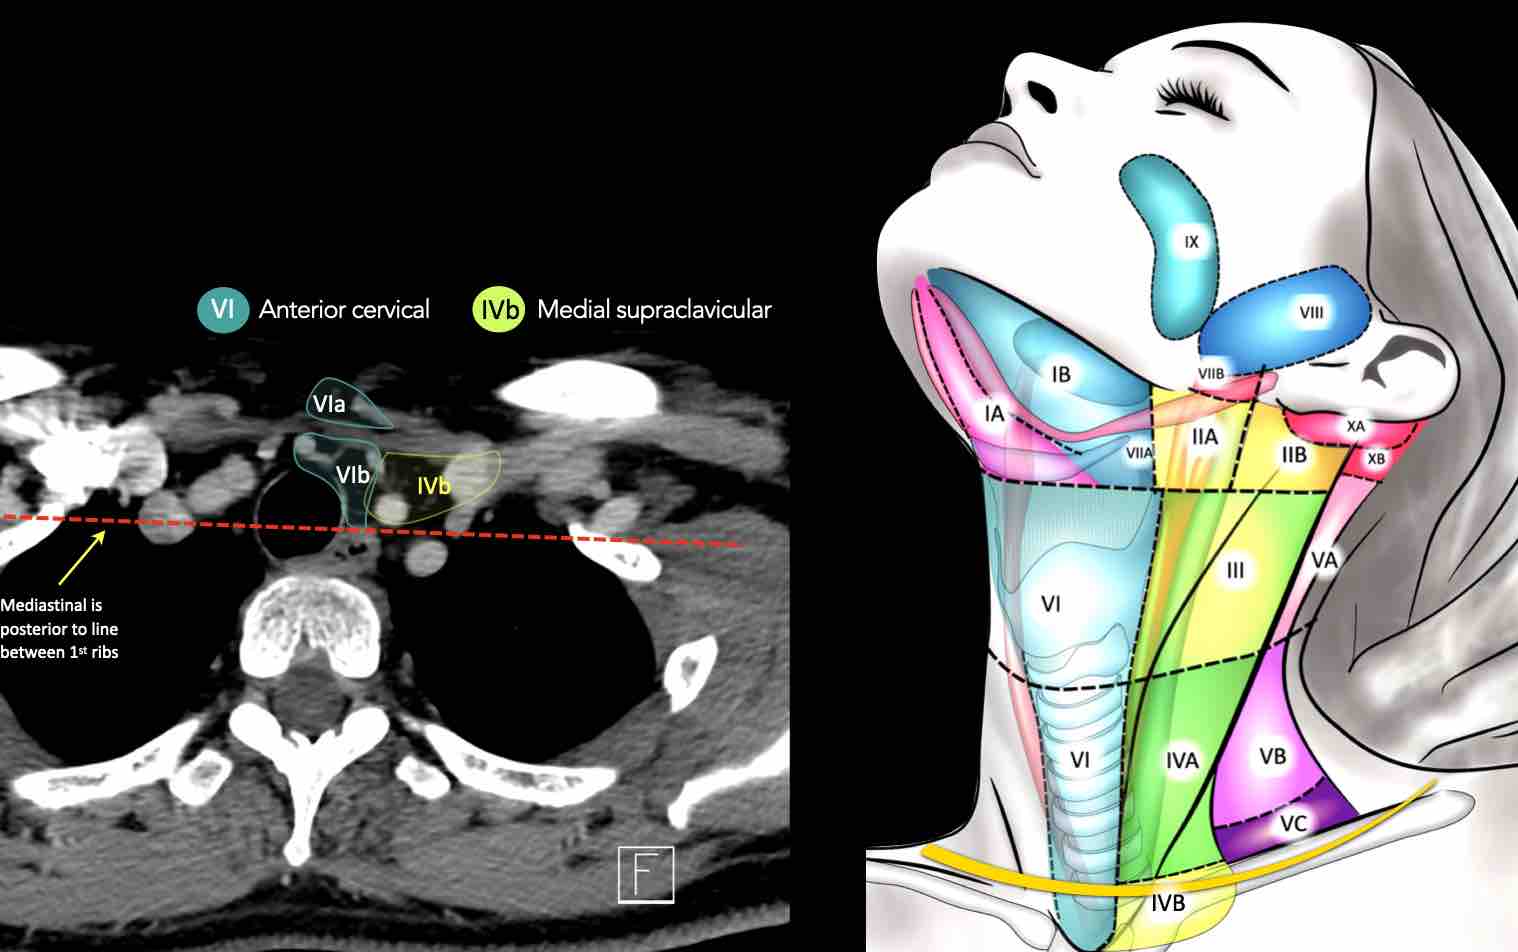

CT Scan Mặt Cắt Ngang (Axial CT)

Các lát cắt CT mặt phẳng ngang tương ứng với hình minh họa tổng quan.

Các lát cắt CT mặt phẳng ngang với hình ảnh chi tiết hơn.

Nhấp vào hình ảnh để phóng to.

IV – Tĩnh mạch cảnh dưới và hố thượng đòn trong

Ranh giới giữa tầng IVa và IVb được xác định tùy ý tại vị trí 2 cm phía trên khớp ức đòn.

Tầng IVb

Các hạch này có nguy cơ chứa di căn từ các ung thư hạ hầu, thanh quản dưới thanh môn, khí quản, tuyến giáp và thực quản cổ.

VI – Cổ trước

Tầng này chứa các hạch tĩnh mạch cảnh trước nông (tầng VIa) và các hạch sâu hơn bao gồm hạch trước thanh quản, trước khí quản, cạnh khí quản và hạch thần kinh thanh quản quặt ngược (tầng VIb).